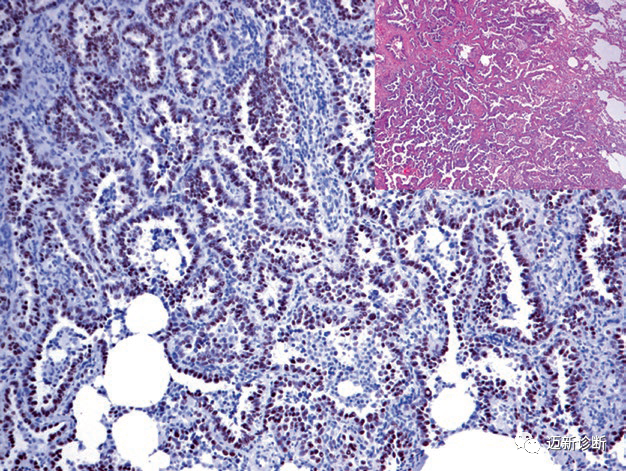

图1. 肺小细胞癌中TTF-1在细胞核强阳性表达。

图2. 肺腺癌中TTF-1在细胞核强阳性表达。

图3. 转移性肺腺癌,免疫组化Napsin A胞质强阳性表达。